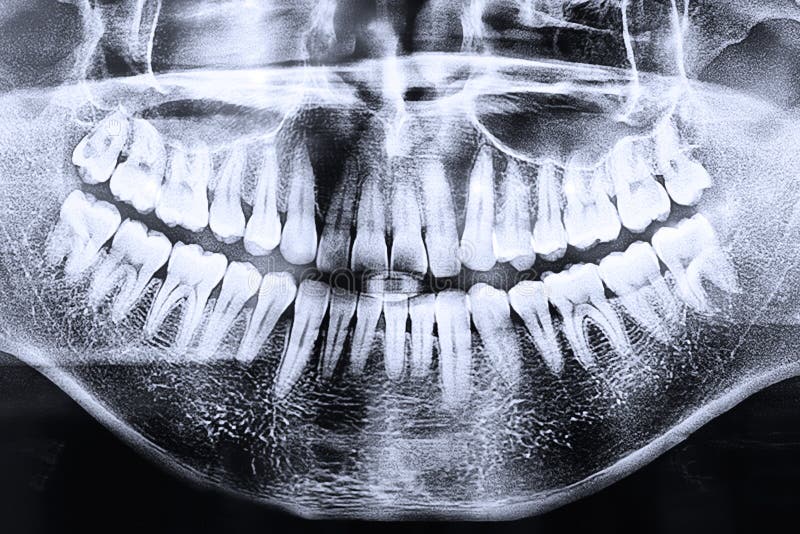

Примеры ортопантомограмм и их анатомия

Раздел: Фотоэссе